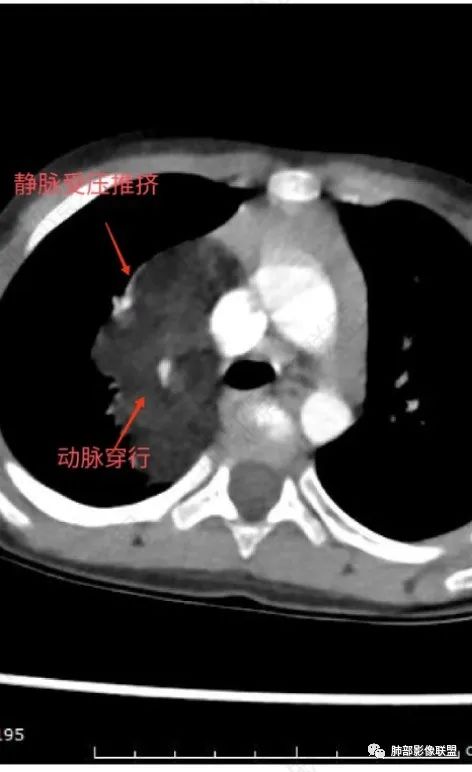

定位:肺内?尖段气管未见明显显示,腔静脉受压向右推移?病灶内可见前段动脉穿行,脂肪密度为主。

肿块起源于右上气管分叉处?强化动脉血管最后汇入右肺动脉上干。

右侧纵隔奇静脉水平起源?压迫上肺,包绕动脉?

病灶属于交界区,主体位于肺内,占位效应明显,前方突入胸壁,胸腺受压变形,胸膜显示欠清楚;病灶包绕上叶肺动脉;似乎有体动脉供血。符合肺内的点:包绕上叶肺动脉分支;符合纵隔的点:前方似乎突入胸壁,与胸腺关系比较密切,但是与上腔静脉的关系提示病灶不支持纵隔来源,前纵隔的常规会将上腔静脉受压后移、外移,这是不符合的。